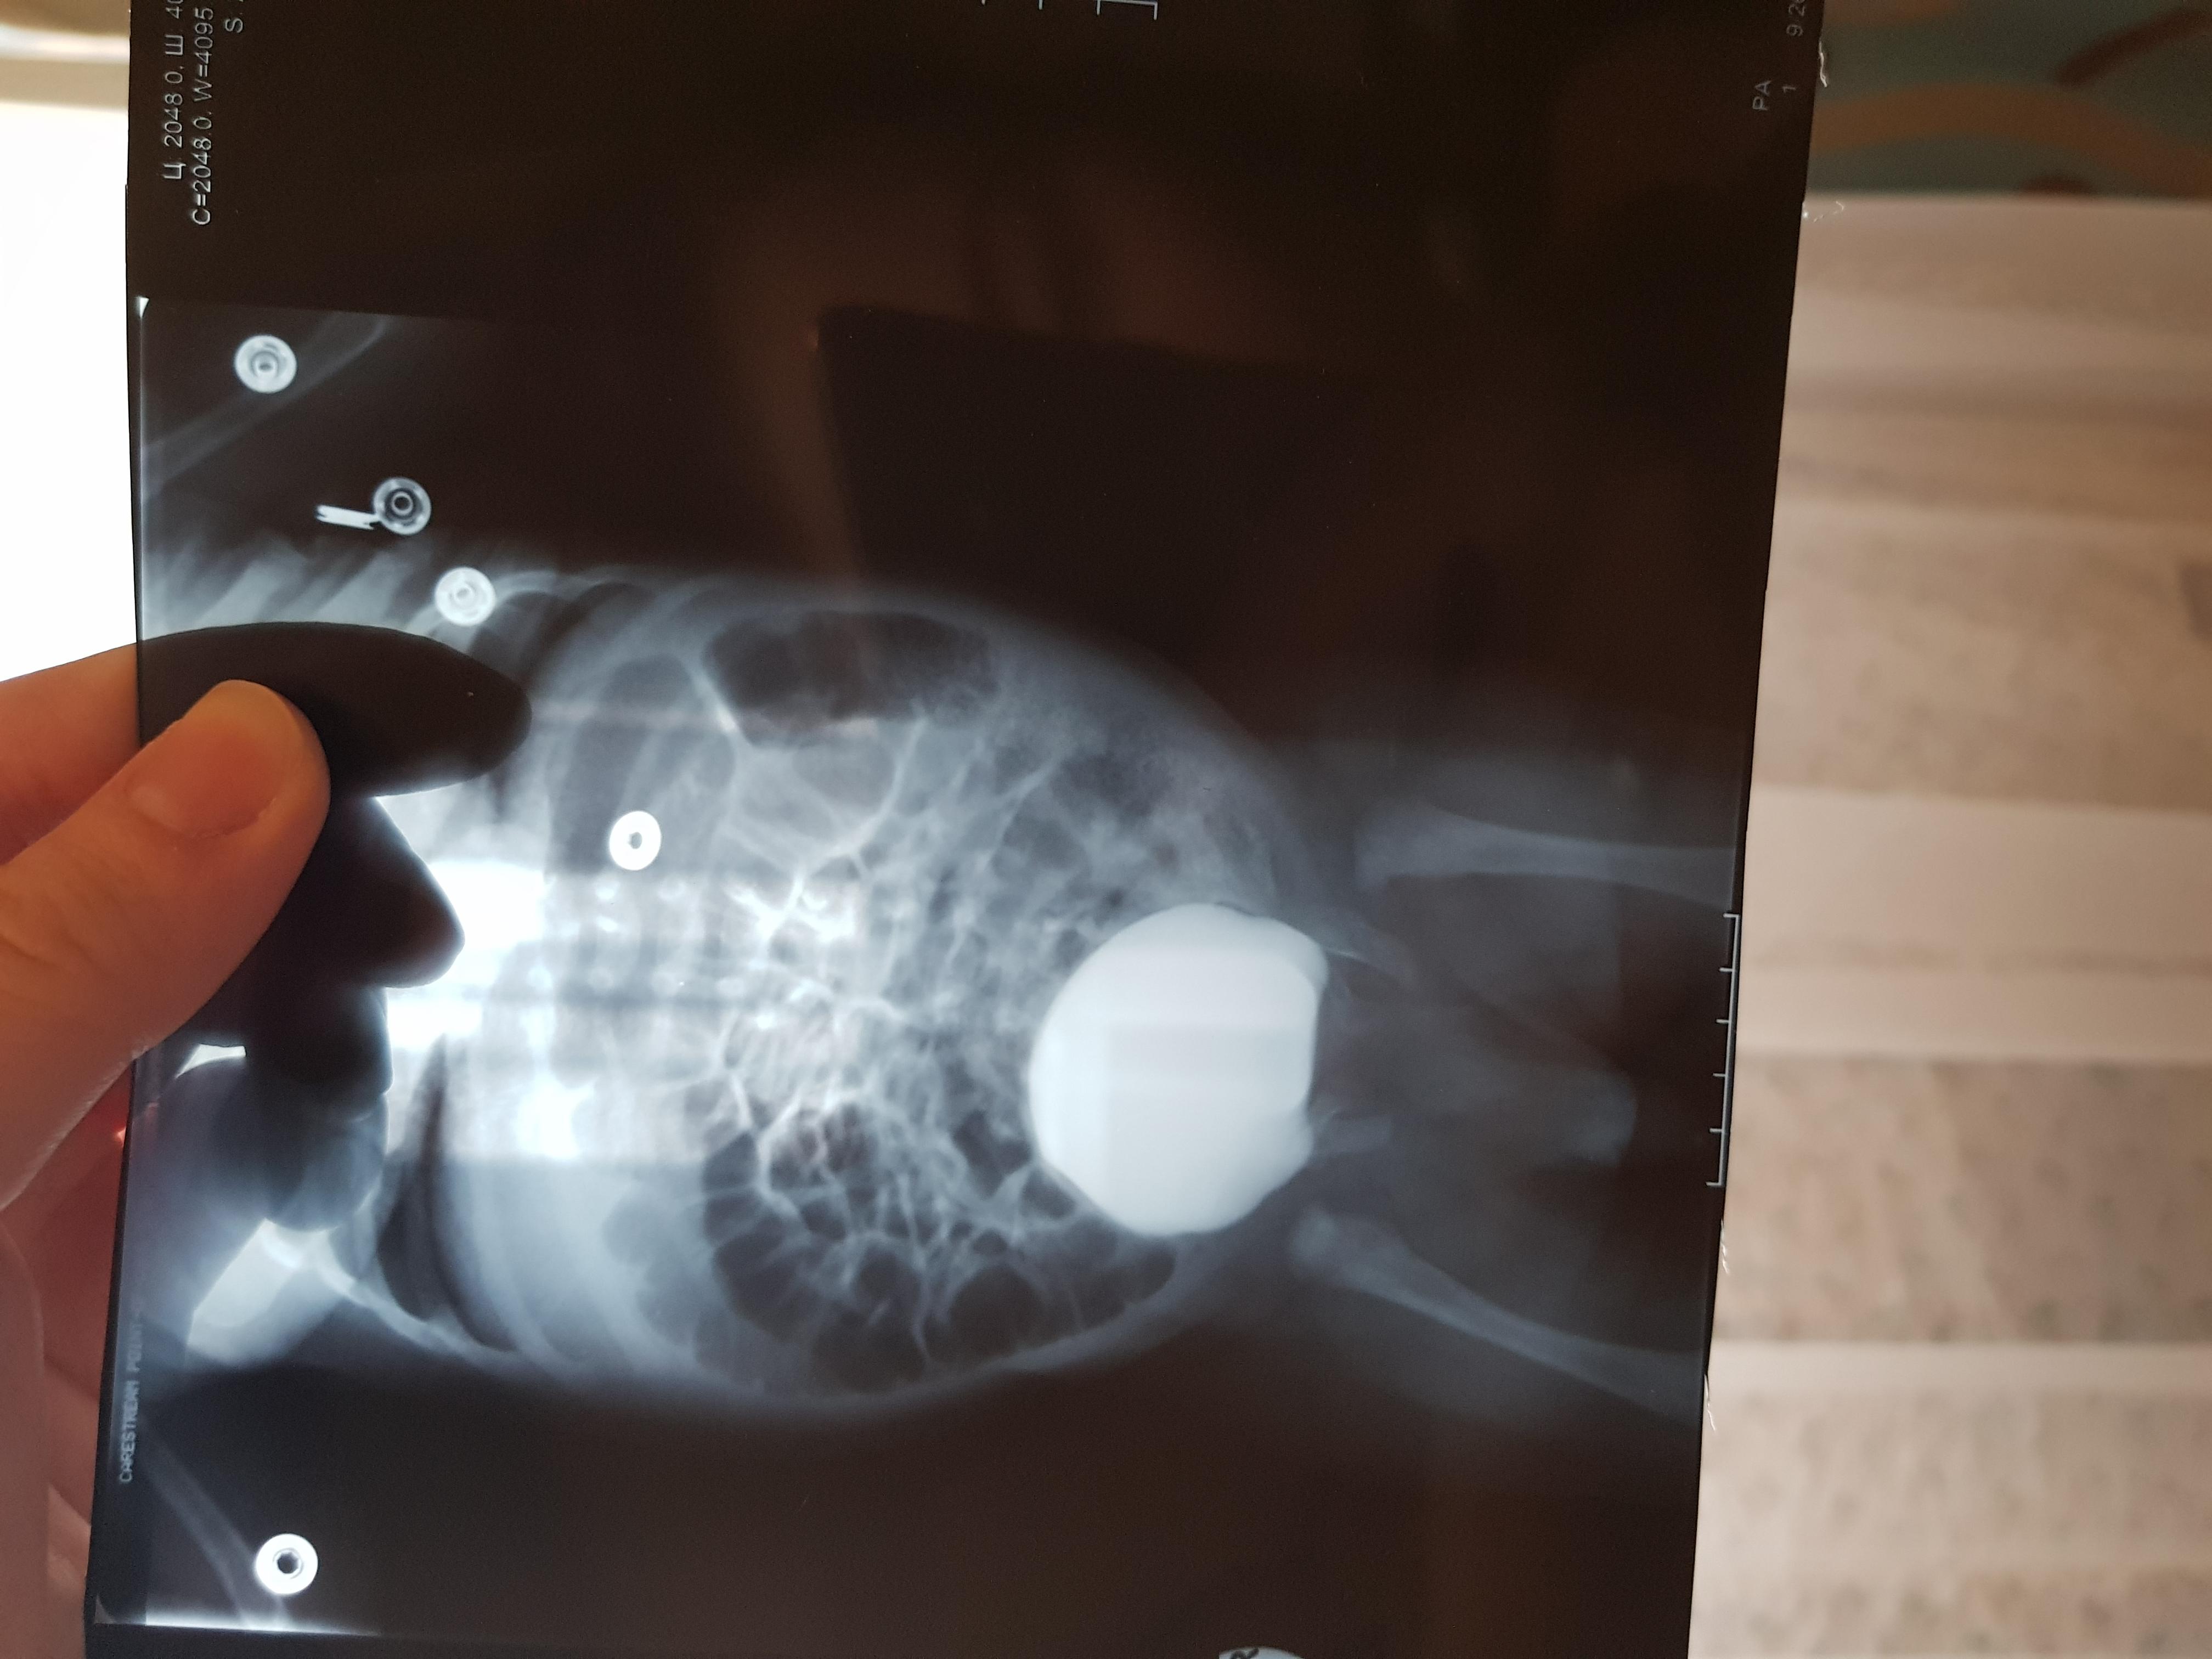

Добрый день! Еще внутриутробно у ребенка обнаружили расширение лоханок.Провели обследование в 1.5 месяца.Поставили диагноз болезнь Ормонда.И назначили консервативное лечение.В 2ух мочеточниках по несколько наростов.рефлюкса не было.Скажиье, возмлжнл что ребенок поосто перерастет?

Болезнь Ормонда (ретроперитонеальный фиброз, забрюшинный фиброз) – хроническое воспаление жировой клетчатки забрюшинного пространства, которое постепенно приводит к компрессии и нарушению проходимости трубчатых структур данного анатомического участка. Чаще всего, в качестве этих тубулярных структур выступают мочеточники.

У меня есть сомнения, что причиной гидронефроза в Вашем случае явилось именно это состояние.

Возможно речь идет о пузырно-мочеточниковом рефлюксе.